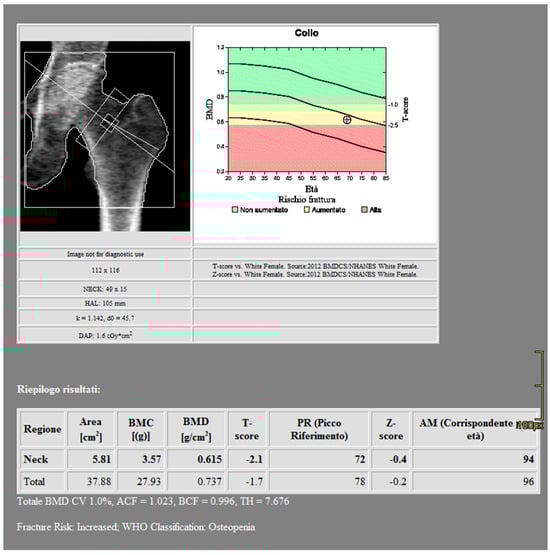

CT images were processed using AW3.2 software (GE Healthcare, Chicago, IL, USA) with a bone window and HAP–fat base material pairing, which highlights structures containing hydroxyapatite. Three-dimensional volume of interest (VOI) measurements were obtained at the lumbar vertebrae (Figure 3) and femoral neck (Figure 4), sampling the trabecular bone while excluding cortical bone regions.

Figure 4. DECT measurements on the femoral neck (ROI5: femoral neck volume measurement). The ROI volume was 858 mm3.